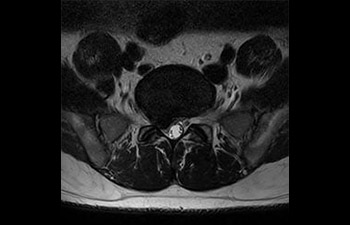

com Compressed SENSE

A equipe de IRM do Hospital Central Kurashiki incorporou o Compressed SENSE à maioria dos protocolos de exames do cérebro, coluna, abdômen e coração do seu Ingenia 1.5T, o que resultou em varreduras de IRM mais rápidas e de alta qualidade, um resultado apreciado por pacientes e pela equipe.